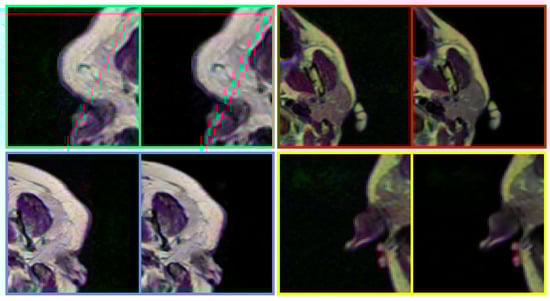

In the real-world scenario, the noise that appeared in the medical images can differ from the synthesized data. Therefore, to push the MID a furthermore, the feasibility of the proposed method has been studied with real-world noisy medical images. As Figure 8 illustrates, the proposed method can notoriously handle the real-world noise and substantially improve the perceptual image quality of noisy medical images by removing blind-fold noise.

Figure 8. Performance of the proposed method in removing noise from real-world medical images. The proposed method can handle real-world noise without producing any visually disturbing artefacts. In each pair, left: Noisy input, Right: Denoised image (obtained by DRAN). Source by: (https://www.kaggle.com/mateuszbuda/lgg-mri-segmentation).